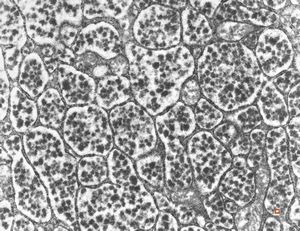

normal seromucinous salivary gland